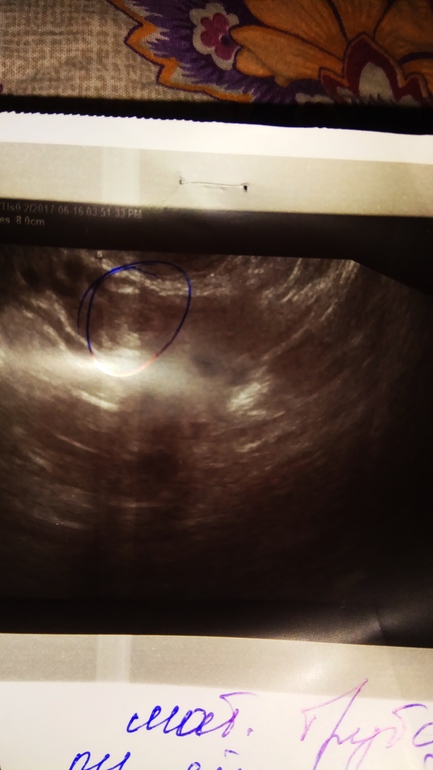

Девчонки,подскажите,что это может быть.Узистка так и не сказала внятно,склоняется к аднекситу в левой трубе.А может это просто фолликул?иоможет кто то сталкивался с таким.

«Рядом с левым яичником виз-ся образование,с утолщенным контуром,просвет жидкостный.ф 19*14мм.а может это внематочная,уже думаю о самом страшном((фото узи

Вот и я о чем . Как увидела ваше , вспомнила своё кольцо . Узистка потом это УЗИ показала она сразу сказала что это кишечника кольцо с жидкостью

Если я не ошибаюсь, если бы у вас была ВБ то образование должно быть в трубе, не в яичнике.